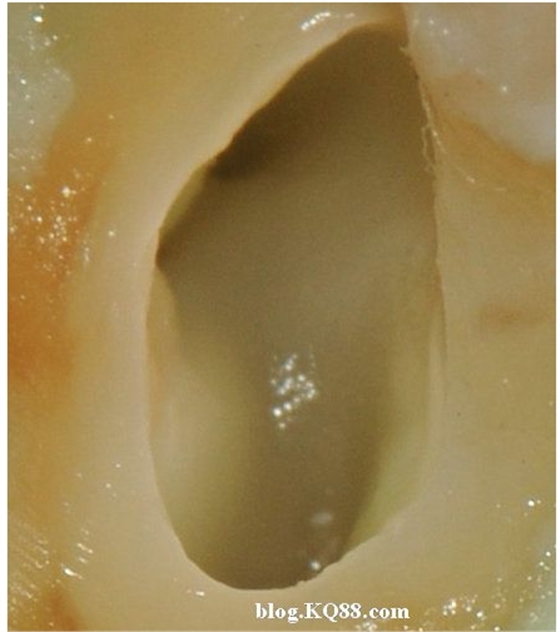

下邊這張圖可以看出氣泡明顯少了,說(shuō)明次氯酸鈉的溶解速度變慢了。

棉球吸除2%的次氯酸鈉,可以看到牙髓明顯的被溶解掉一部分

換用5%左右的次氯酸鈉很快髓腔內(nèi)的牙髓溶解了

單靠次氯酸鈉作用后的髓腔